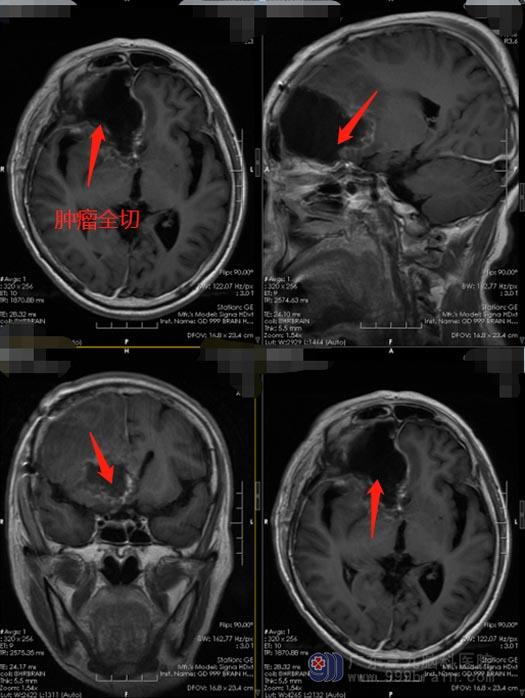

了解病情后,家人便积极地为曾阿姨寻求治疗。针对患者的具体病情,广东三九脑科医院神经外五科鲁明主任带领治疗团队进行了多次的术前讨论。额叶位于大脑的前部,额叶受损可以引起随意运动、言语、颅神经、植物神经功能及精神活动等方面的障碍,所以在手术中既要尽可能多的切除病灶,又要最大程度保留患者的正常脑功能。最终决定在唤醒麻醉下为曾阿姨行“右额胶质瘤切除术”,术中将患者从麻醉状态中唤醒,让其完成与各功能相关的监测任务,并通过电刺激的方式精确识别和区分大脑重要功能区的位置,使术者能够通过从非功能区区域入手切除病灶。手术过程顺利,术中曾阿姨积极配合医生,语言、肢体功能都保留良好。

术后,曾阿姨神志清楚,活动好,记忆力较以前有所改善。病理结果是额叶胶质母细胞瘤,WHO IV级,后期还需要接受进一步的化疗。